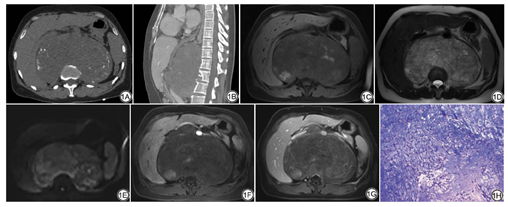

影像学检查:CT示腹膜后(约膈顶至双肾平面)一巨大肿块影,肿块半包绕T10~L2椎体,大小约17.7 cm×10.6 cm×14.8 cm,边界清楚,平扫呈混杂稍低密度影,内见多发条状、点状高密度影(图1A),增强后呈轻度不均匀强化;L1椎体前份骨质破坏(图1B),T12~L3椎体前缘见骨质硬化边。MRI示腹膜后肿块于T1WI呈混杂稍低信号,内见斑片状低信号影及高信号影(图1C);T2WI呈混杂高信号,内见线状低信号影(图1D);扩散加权成像(diffusion weighted imaging, DWI)呈不均匀高信号(图1E),表观扩散系数(apparent diffusion coefficient, ADC)值降低;增强后肿块轻~中度不均匀强化,分隔及包膜延迟强化(图1F、1G)。肿块推压胰腺、腹主动脉、下腔静脉及肾血管向前移位,推压双肾向下前移位,推压双侧腰大肌上份向外移位。L1椎体信号改变与上述病灶相似。

患者在全麻下行腹膜后巨大肿瘤切除术+腹主动脉、门静脉、腔静脉、左右肾静脉松解悬吊术+第一、第二肝门悬吊+膈肌肿瘤切除术。术中显示肿块位于十二指肠、胰头、肾脂肪囊之间,与下腔静脉、腹主动脉、门静脉关系密切,与膈肌粘连较重。大体标本示肿块呈灰白、灰红、灰黄色,总大小约22 cm×20 cm×4.5 cm,局部可见包膜。镜下(HE ×100)见瘤细胞呈条索状、网状排列,并漂浮在淡蓝色黏液样间质中(图1H)。免疫组化:Ki-67(10%+)、NSE(局灶+)、EMA(+)、CKL(+)、CK广(+)、CD68(-)。术后病理诊断:腹膜后脊索瘤(经典型),肿瘤侵犯骨组织。术后5个月复查肿瘤复发,邻近骨质破坏严重。

本例患者在CT平扫上见多发高密度影,提示富含骨质或钙化成分,邻近的L1椎体呈溶骨性骨质破坏,骨质破坏周围及T12、L2~L3椎体前缘见骨质硬化边。MRI示肿块于腹侧面呈膨胀性生长,面向骨及肌群等组织侧可见足状突起,提示肿块呈对抗性的侵袭性生长,与方汉贞等[4]对骶尾部脊索瘤的研究一致。T1WI上肿块以稍低信号为主,内见斑片状低信号影及高信号影,低信号影提示骨质或钙化,高信号影提示出血可能。T2WI上呈分叶状、结节状改变,其内见线状低信号的分隔及高信号的黏液间质。DWI示扩散不均匀受限,与瘤细胞间隙狭窄,影响细胞外水分子扩散有关。增强扫描后动脉期呈轻~中度不均匀强化,延迟期分隔及包膜延迟强化,呈“蜂房状”改变。肿块周围脏器及大血管(下腔静脉、腹主动脉、双侧肾血管)受推压、移位。既往有文献[5]报道高达79%的脊索瘤可导致颅内大动脉移位或受包绕。综上,发生于腹膜后的脊索瘤与发生于其他部位的脊索瘤影像表现一致,主要表现为以下几点:(1)肿瘤边界清楚,可见假包膜;(2)CT平扫上见高密度的钙化或骨质成分,邻近骨质受侵;(3)T1WI以混杂稍低信号为主,其内见多发高信号影;T2WI上肿瘤呈分叶状、结节状,并以混杂高信号为主,内见条状的低信号分隔;(4)增强扫描后肿瘤呈“蜂窝状”改变;(5)邻近器官及大血管受推压、移位。